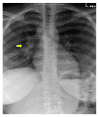

We report a case of a Somali refugee who presented in the second trimester of her first pregnancy with a four-week history of gradual right-sided sensomotoric hemisyndrome including facial palsy and left-sided paresis of the oculomotorius nerve causing drooping of the left eyelid and double vision. Cranial magnetic resonance imaging revealed a solitary brainstem lesion. Upon detection of hilar lymphadenopathy on chest X-ray (CXR), the diagnosis of disseminated tuberculosis with involvement of the central nervous system was confirmed by PCR and treatment induced with rifampicin, isoniazid, pyrazinamide, and ethambutol. The patient had a steady neurological improvement and a favorable pregnancy outcome.